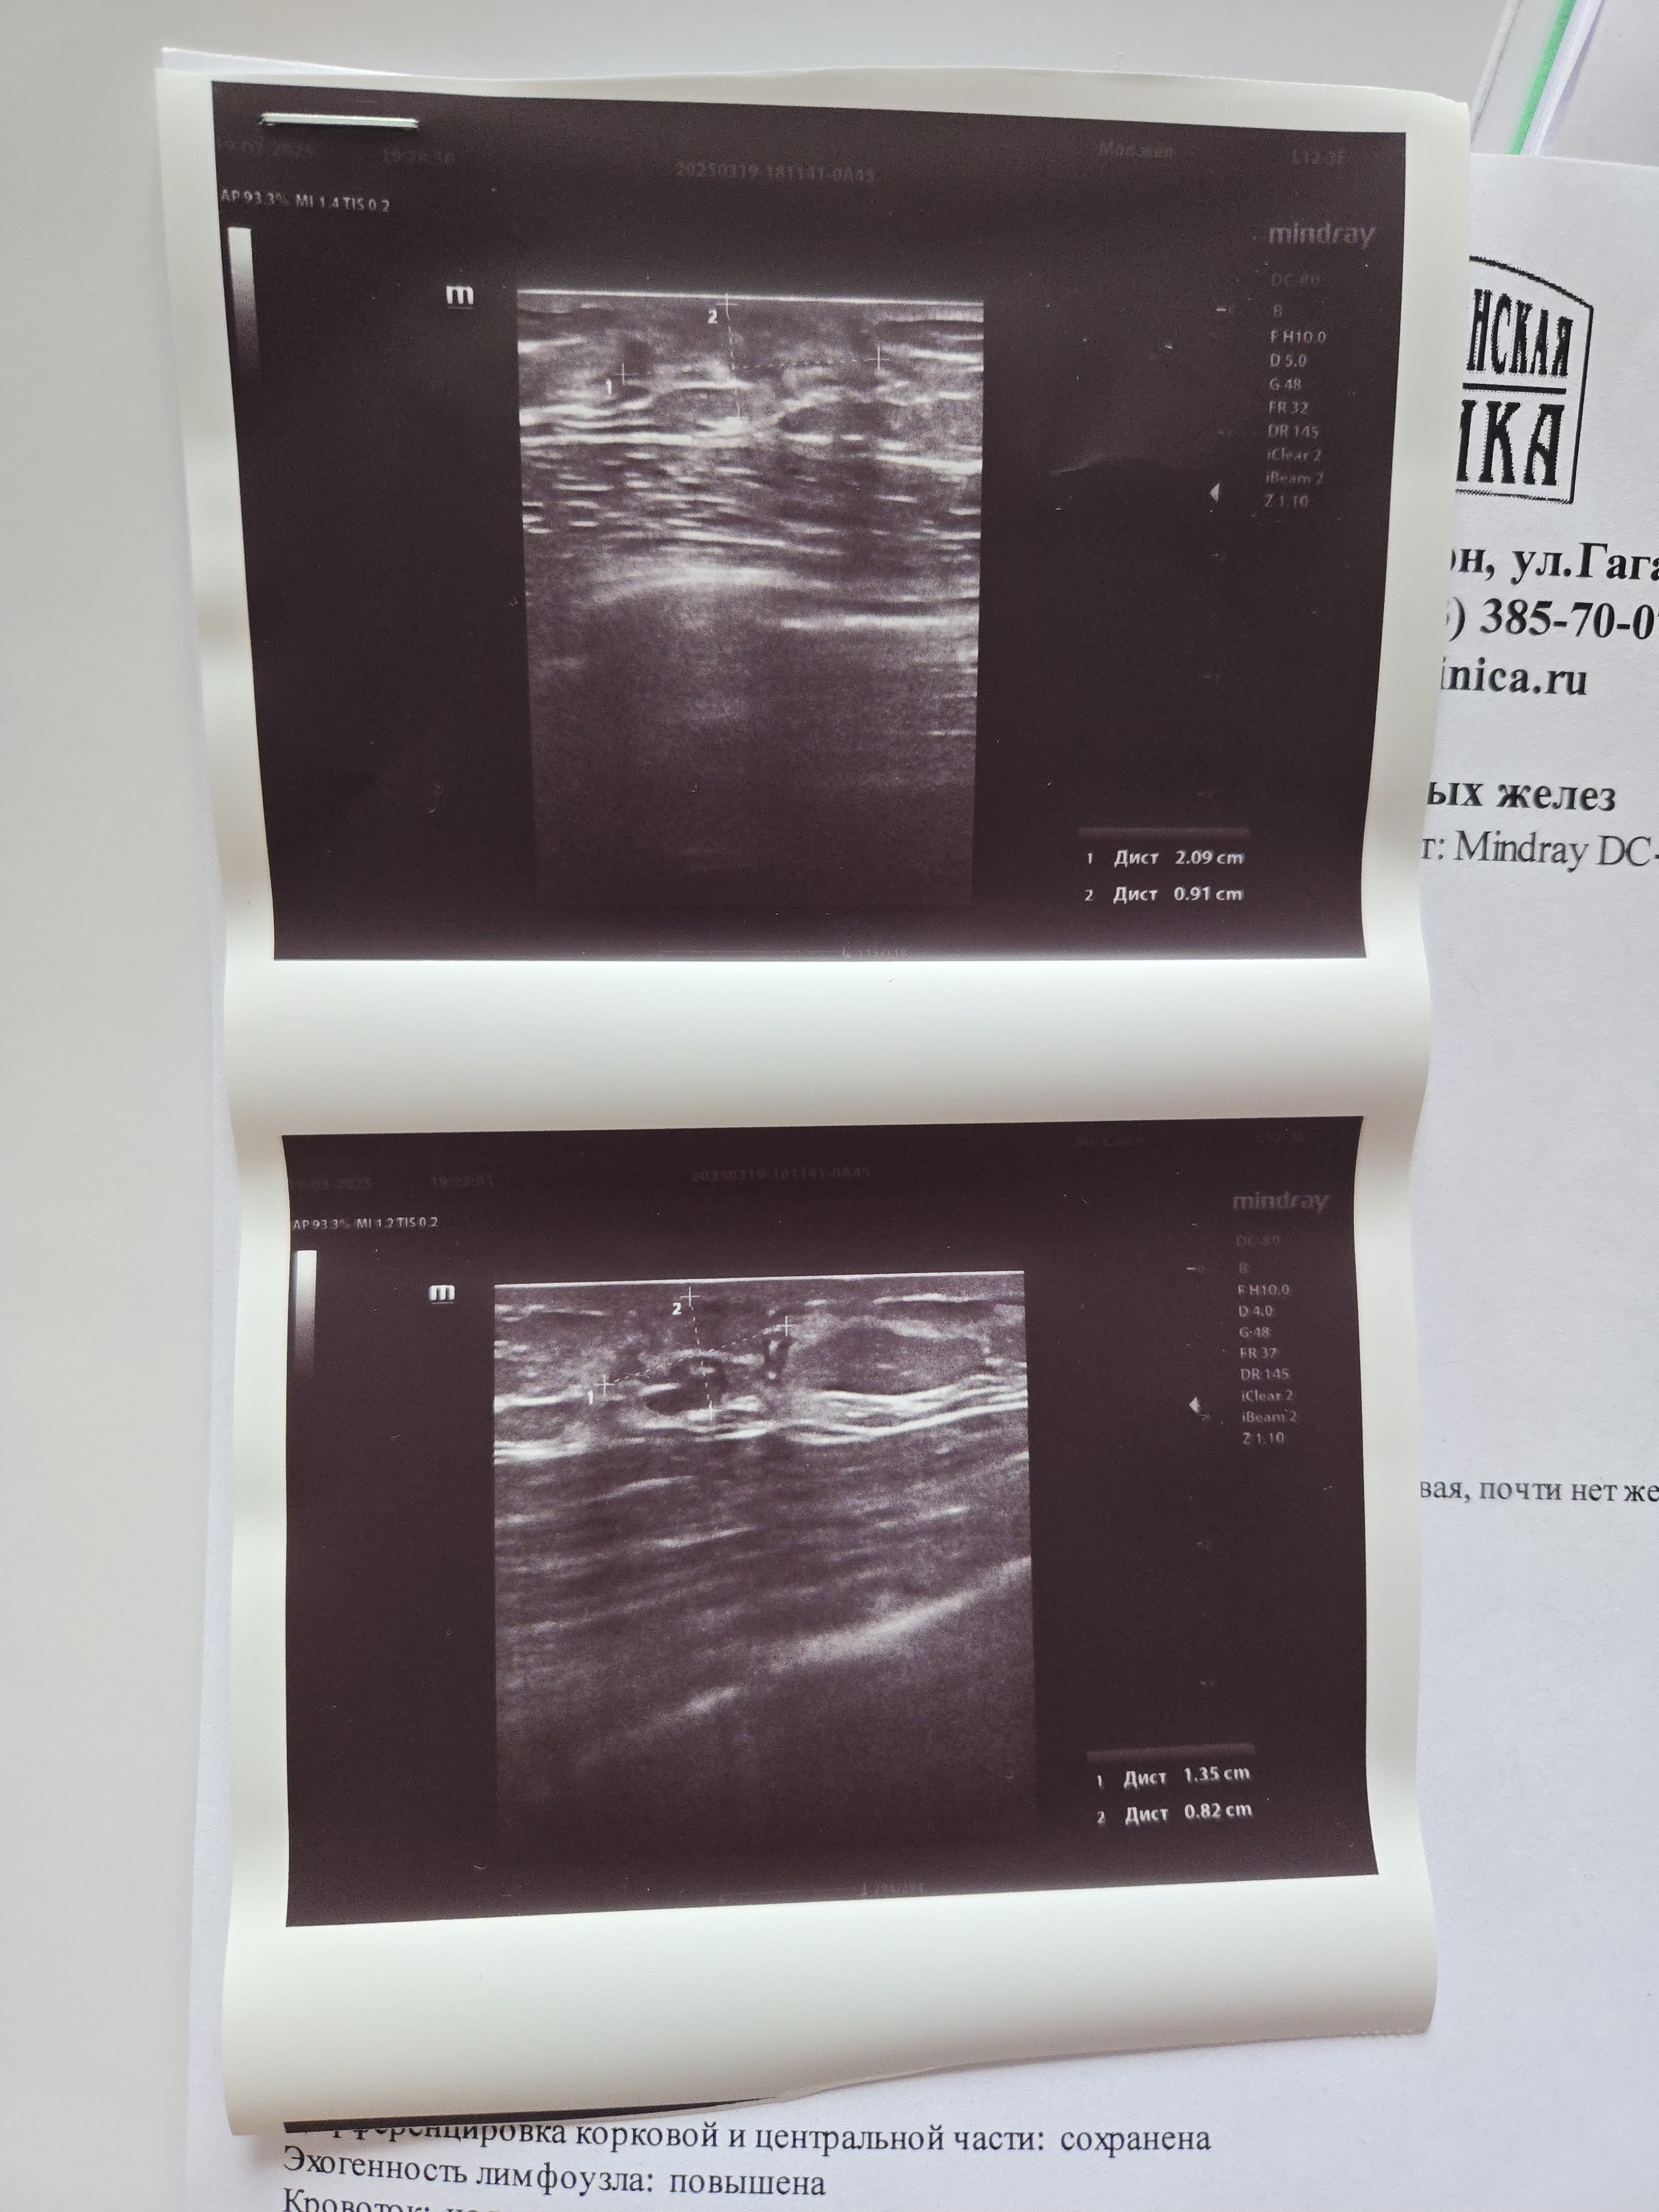

носить только мешковатую одежду и то быдло сиськи палит

Мне когда делали я на монитор смотрел, и просил показать и объяснить, а там даже без мед образования видно что что-то не так, потом ещё попросил распечатать мне изображения.

Если хоть чуть чуть не забить хуй то не обманут.